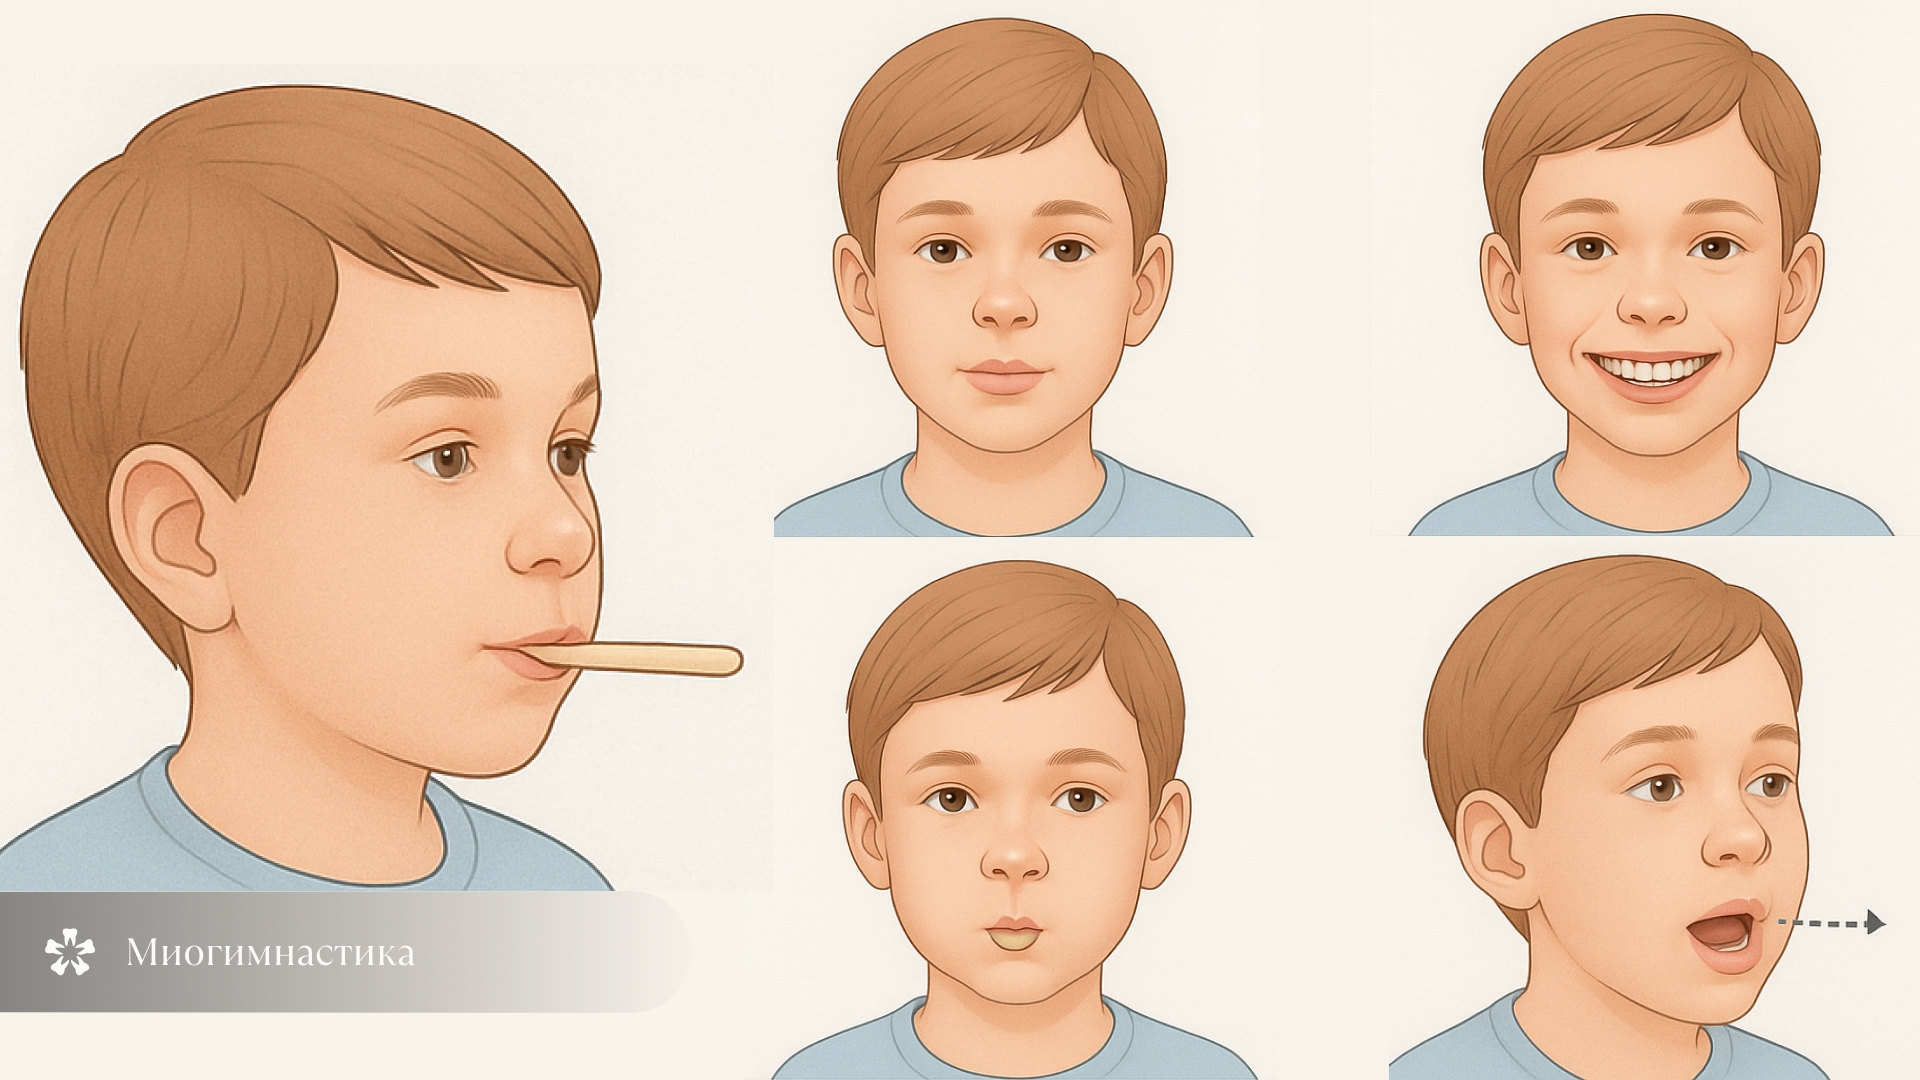

| 3–5 лет | Миогимнастика, профилактика, съемные аппараты |

Миогимнастика

Если ребенок выставляет нижнюю челюсть вперед, полезно подключить миогимнастику — комплекс упражнений для мышц лица, языка. Она помогает устранить вредные привычки и нормализовать функцию мышц. Метод подходит детям любого возраста, не вызывает дискомфорта. Упражнения делают дома или на курсах (от 5 тысяч рублей), а выполнять их нужно весь период коррекции.